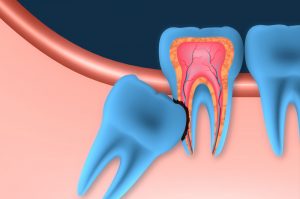

Affordable Wisdom Tooth Extractions in Brampton – Pricing & Options Explained Worried about the cost of removing a wisdom tooth? You’re not alone. Many patients delay wisdom tooth extraction due to uncertainty about pricing — but doing so can lead to worse problems down the road. At Polaris Dental in